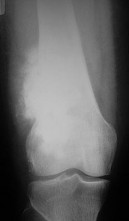

A 15-year-old male presents with deep knee pain awakening him at night. Radiographs show a permeative destructive lesion in the distal femoral metaphysis with a 'sunburst' periosteal reaction and Codman's triangle.

Biopsy confirms high-grade conventional osteosarcoma. What is the most critical prognostic factor for long-term overall survival in this patient?

Explanation

For localized high-grade osteosarcoma, the most important prognostic indicator is the histologic response to neoadjuvant chemotherapy. This is evaluated during the definitive resection. A 'good response' is typically defined as greater than 90% or 99% tumor necrosis. Patients who achieve this level of necrosis have a significantly improved disease-free and overall survival rate compared to 'poor responders' who have extensive viable tumor cells remaining.